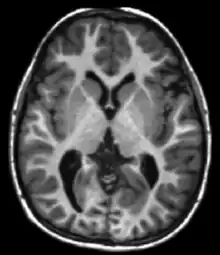

Magnetic resonance imaging (MRI) is a medical imaging technique used in radiology to form pictures of the anatomy and the physiological processes of the body. MRI scanners use strong magnetic fields, magnetic field gradients, and radio waves to generate images of the organs in the body. MRI does not involve X-rays or the use of ionizing radiation, which distinguishes it from computed tomography (CT) and positron emission tomography (PET) scans. MRI is a medical application of nuclear magnetic resonance (NMR) which can also be used for imaging in other NMR applications, such as NMR spectroscopy.[1]

MRI is widely used in hospitals and clinics for medical diagnosis, staging and follow-up of disease. Compared to CT, MRI provides better contrast in images of soft tissues, e.g. in the brain or abdomen. However, it may be perceived as less comfortable by patients, due to the usually longer and louder measurements with the subject in a long, confining tube, although "open" MRI designs mostly relieve this. Additionally, implants and other non-removable metal in the body can pose a risk and may exclude some patients from undergoing an MRI examination safely.